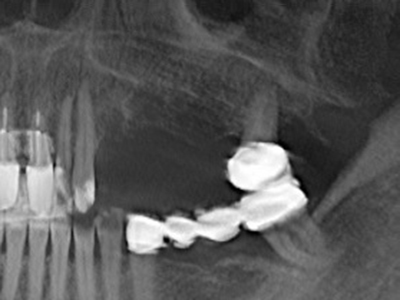

Abb. 11: Das postoperative OPTG veranschaulicht die vertikale Augmentation und Sinusbodenelevation.

Die Präparation des lateralen Fensters bei der externen Sinusbodenelevation stellt gerade für chirurgisch unerfahrene Implantologen eine große Herausforderung dar. Die knöcherne Bedeckung der Kieferhöhle ohne eine Verletzung der darunterliegenden Schneider’schen Membran abzutragen ist dabei nur ein Teil der Operation – nach Schaffung eines ausreichenden Zugangs muss die Kieferhöhlenschleimhaut vorsichtig mobilisiert werden, um Raum für das einzubringende Material bzw. die Implantate zu schaffen. In dieser Indikation ist die Piezochirurgie zweierlei hilfreich: zum einen kann durch Verwendung diamantierter Instrumente eine selektive Knochenabtragung erfolgen und die darunter liegende Schleimhaut bleibt bei vorsichtiger Vorgehensweise intakt. Zum anderen unterstützen die Ultraschallfrequenzen zusätzlich eine komplikationslose Ablösung der Schleimhaut – sie werden durch spezielle stumpfe Ansätze in den Spaltraum zwischen Schleimhaut und Kieferhöhlenboden übertragen (Cassetta, Ricci et al. 2012, Pereira, Gealh et al. 2014) (Rickert, Vissink et al. 2013). So erscheint es nicht verwunderlich, dass in aktuellen Übersichtsarbeiten über die externe Sinusbodenelevation neben der Verwendung von rauen Implantatoberflächen und dem Einsatz von Knochenersatzmaterialien auch der Einsatz von piezoelektronischen Geräten als positiv bewertet wird (Wallace, Tarnow et al. 2012).